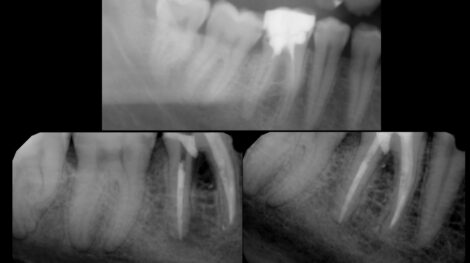

Usunięcie złamanego narzędzia i wyleczenie zmiany zapalnej

Usunięte narzędzie – pilnik H